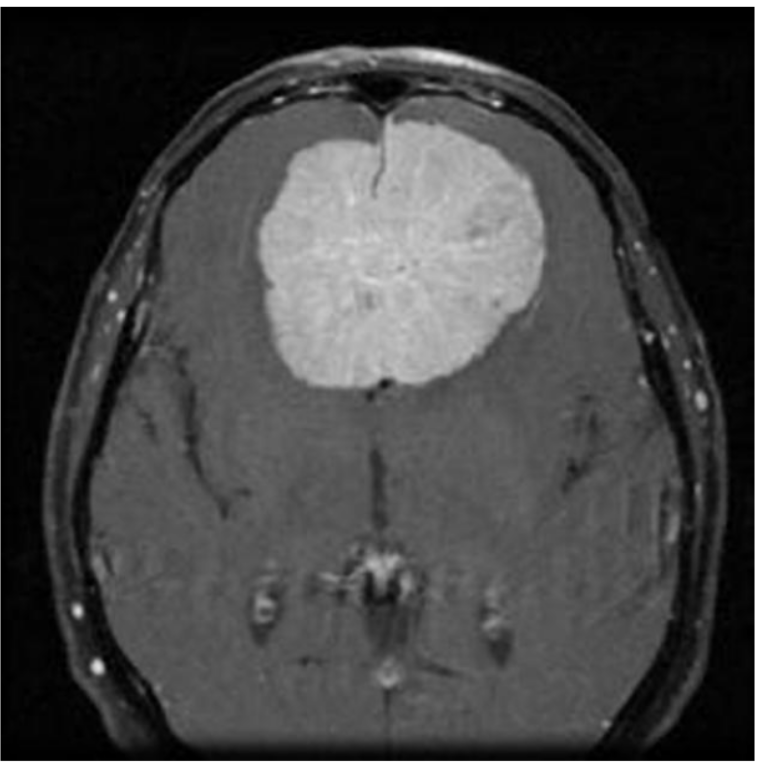

MRI Image MRI Image

Just like humans have certainty when answering questions, my model's output is a representation of how confident it is in its answers. The two images on the right are what my program outputs when prompted with an image. The MRI scan is the test image, and the graphs show its certainty in the answers. The top image shows a certain prediction. In this guess, the blue bar shows that the model is 100% certain that there is no tumor in the MRI scan. Compared to the bottom photo, the model is guessing a few different types of tumors.

After training my model on the 5000 images, I ran through a testing set. Testing set images come from the same source as the training set. Although they are different images, they will be of the same style and quality as the training. I ran through 10 testing images, and they were all predicted accurately with nearly 100% certainty in all of the responses. This shows that AI has the capability of diagnosing tumors with very high accuracy and speed when trained properly.

I eventually ran into a few setbacks with my model, which helps highlight the issues of using AI for detecting tumors. After I ran my testing set with high accuracy, I decided to find my own images from outside sources to test. I pulled one MRI scan per each type of tumor and one for no tumor. These images came from various journal articles. Once the images were run through the model, it was immediately apparent that the accuracy and confidence of the model dropped. The model was able to guess no tumor and meningioma accurately with 100% certainty. My program had issues detecting the pituitary and glioma. For the glioma, for example, the model predicted that it was a meningioma with over 60% certainty, then no tumor with about 35% certainty, and lastly a glioma with a sliver of certainty. The google slides below show the results from the testing set and from outside sources.